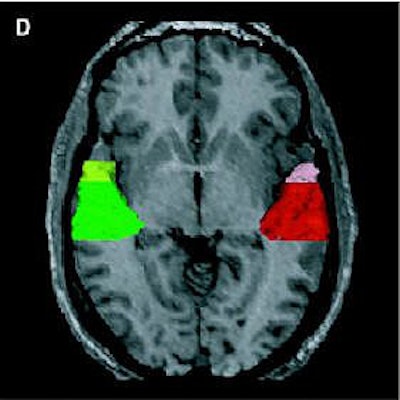

| Above, regions of interest (ROI) examined in MRI study of patients with first-episode schizophrenia or affective psychosis and normal comparison subjects. Top (A) is a 1.5-mm coronal slice of the temporal lobe; the ROI used to evaluate the temporal structures are outlines. The gray matter of the superior temporal gyrus is shown in red (subject left) and green (subject right); more medially, the amygdala-hippocampal complex is shown in orange (left) and blue (right) with the parahippocampal gyrus underneath in pink (left) and purple (right). Below, a left lateral view of a 3D reconstruction of the cortical surface with the anterior superior temporal gyrus (light pink) and posterior superior temporal gyrus (red). |

| Same subject. Above and below, axial MRI is used to present top-down views of the 3D reconstruction of the amygdala-hippocampal complex and parahippocampal gyrus. All images: Figure 1, Hirayasu Y, Shenton ME, Salisbury DF, et al. "Lower Left Temporal Lobe MRI Volumes in Patients with First-Episode Schizophrenia Compared with Psychotic Patients With First-Episode Affective Disorder and Normal Subjects," (Am J Psychiatry 1998; 155:1384-1391). |

![]() |